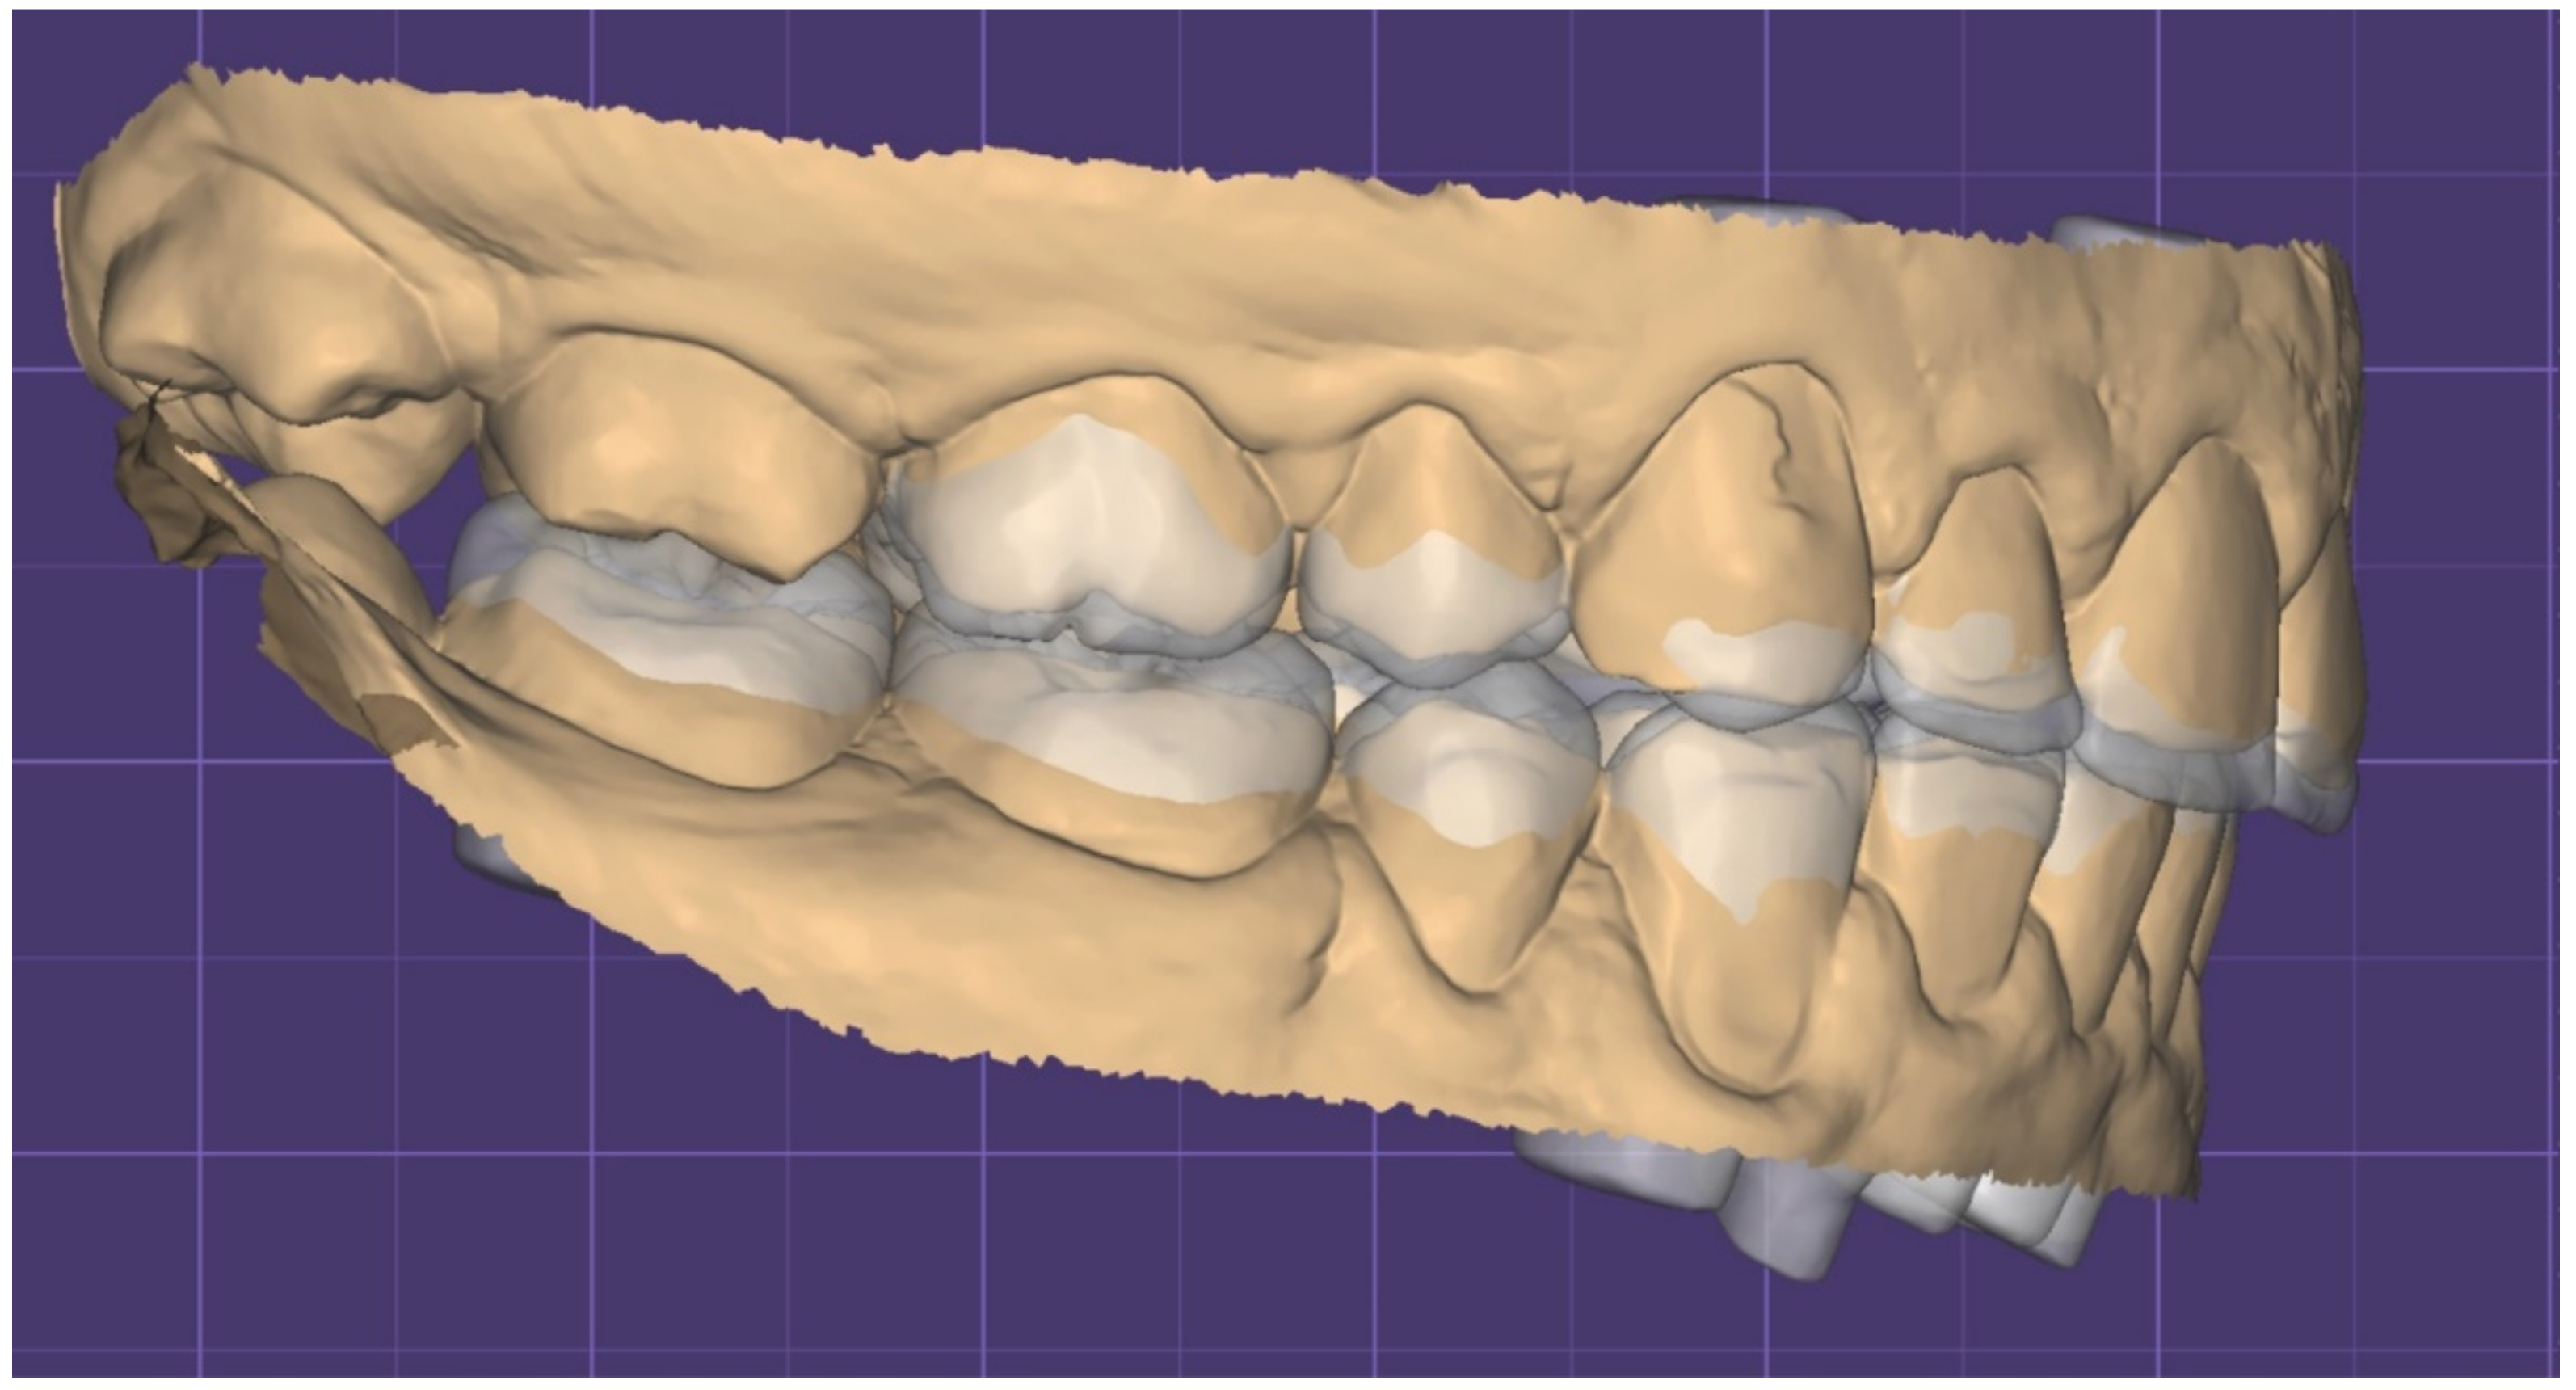

2. Clinical Report

2.1. Planning Phase

2.2. Restorative Phase